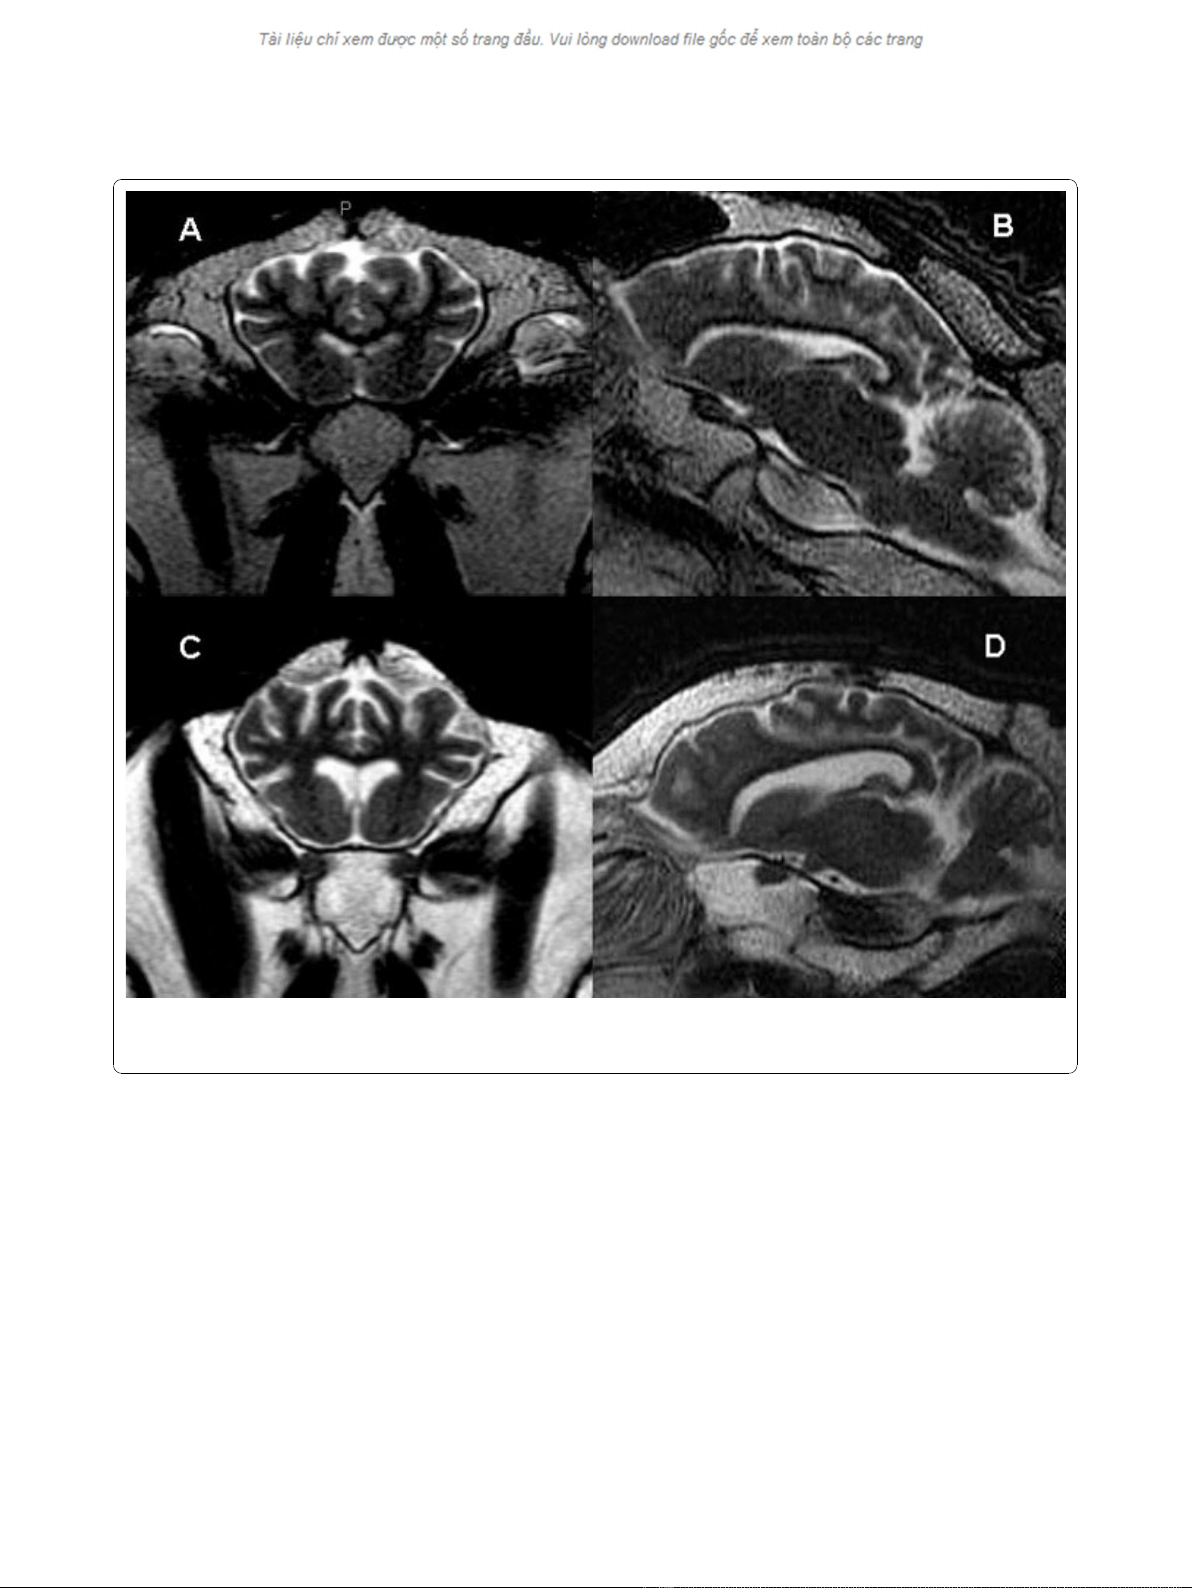

As seen in Figure 2, the most severely affected clinical

animals had hyperintense adipose tissue, predominantly

within the medullary cavity of the skull and around the

retropharyngeal lymph nodes, corresponding with serous

atrophy secondary to emaciation. There was also mild

subjective enlargement of the lateral ventricles with sul-

cal prominence in the most clinically affected sheep

indicative of diffuse cerebral atrophy (Figure 2). This

Figure 2 Axial and sagittal MR images of a normal control sheep (A and B) compared to the most clinically affected animal in the

study (C and D). The sulcal prominence and enlarged lateral ventricles indicative of diffuse cerebral atrophy are seen in the scrapie affected

sheep.